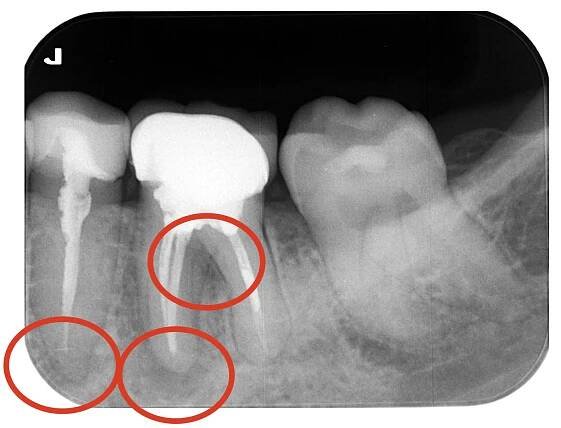

【精密根管治療 】|目白デンタルクリニック|目白駅徒歩3分|土日診療